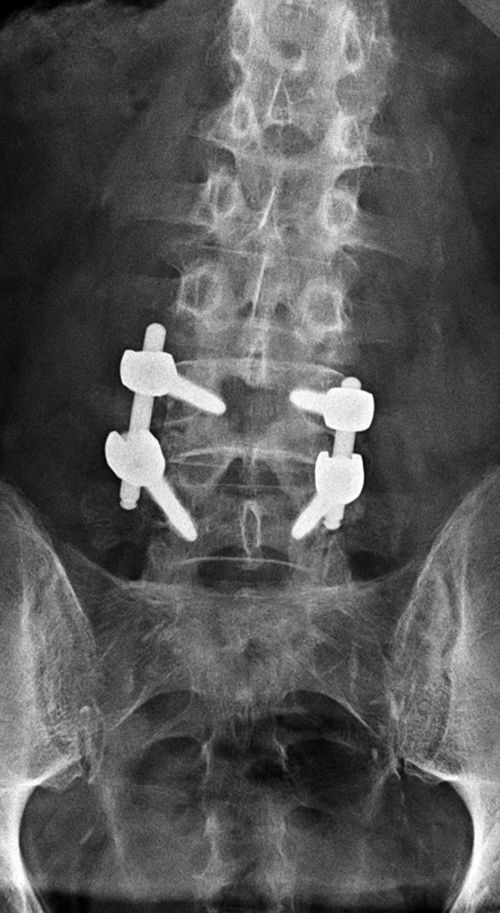

Lumbar spine bony disk strut, pedicle screws, and pedicle rods (AP view) |

20 year-old woman with L1 vertebral body compression fracture treated with T12-L2 posterior spinal fusion using pedicle screws at T12 and L2 with connecting rods on each side. |

There are also bilateral pedicle screws and connecting rods above and below the level of the fracture. |